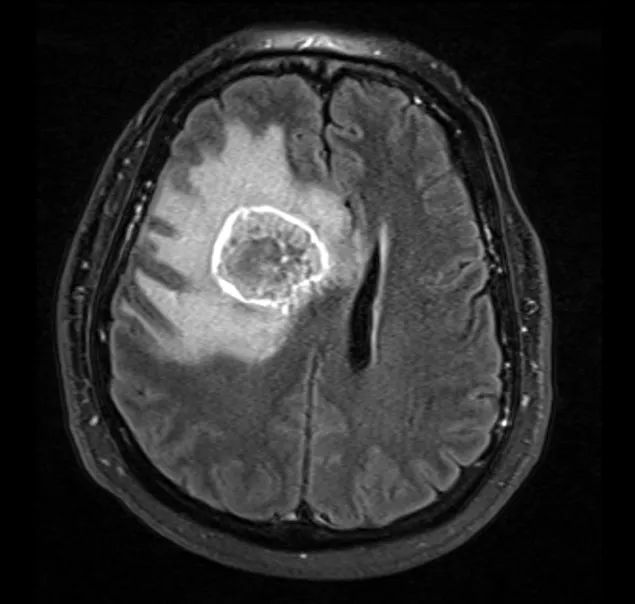

患者为55岁男性,因“跌倒频率增加和左侧肢体无力1周余”就诊。 3年前患者曾于外院行肺癌切除术,但患者后来失访,且无法明确癌变性质和分期。 入院时神经系统查体无异常。 外院头颅CT见颅内出血灶,胸腹盆腔CT未见异常。 立体定向颅内病变活检提示肿瘤为低分化转移癌,细胞标志物检测考虑鳞状细胞癌。

术后患者安返神经ICU。 术后使用地塞米松并于1周内迅速减量撤药。 使用左乙拉西坦500mg bid预防性抗癫痫。 术后第1天复查MRI见肿瘤近全切。

最终病理与活检结果一致,均为转移性低分化癌。 术后第5天患者出院回家,无神经功能障碍,残余肿瘤计划行立体定向放疗,同时建议患者肿瘤科随诊,以处理系统性病变。